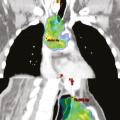

Tableaux et figures